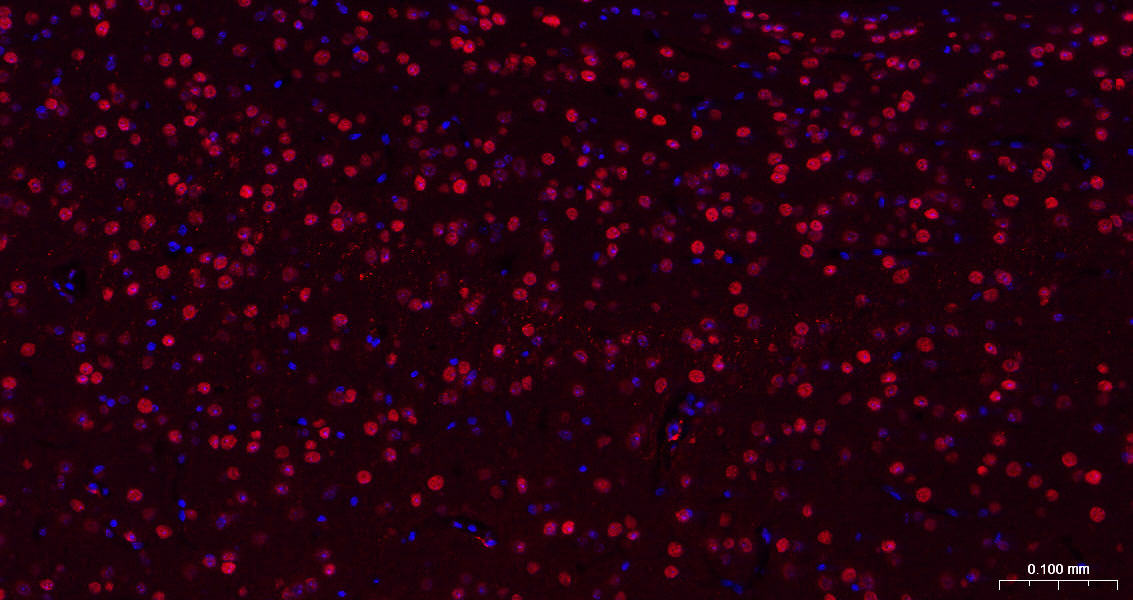

Paraformaldehyde-fixed, paraffin embedded Human Cerebrum; Antigen retrieval by boiling in sodium citrate buffer (pH6.0) for 15 min; The section was incubated with HES1 Monoclonal Antibody, Unconjugated (bsm-52568R) at 1:200 overnight at 4°C. Followed by conjugated Goat Anti-Rabbit IgG antibody (Red, bs-0295G-BF594), DAPI (blue, C02-04002) was used to stain the cell nuclei.